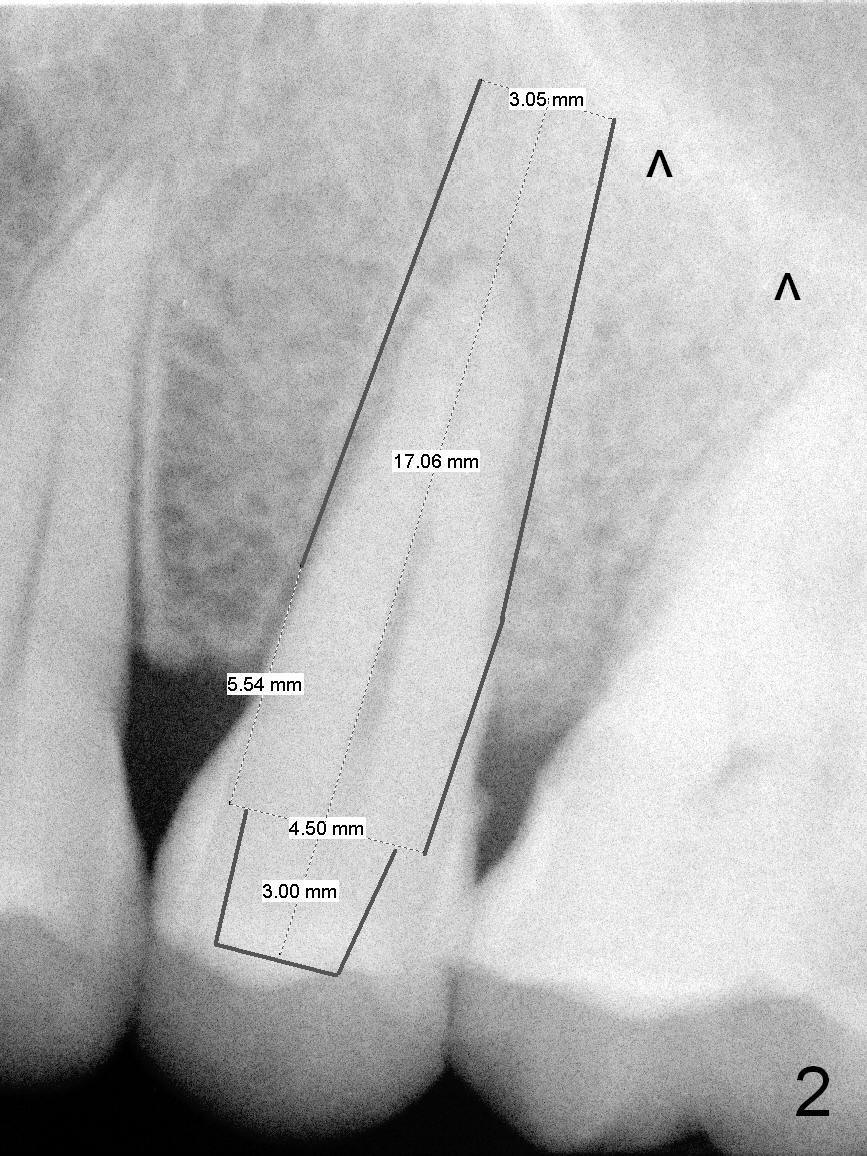

A 47-year-old man returns to clinic with chief complaint "top left tooth chips". Exam reveals subgingival fracture of the lingual cusp of the tooth #13 (Fig.1). A 4.5x17 mm tissue-level implant and 3.5x3 mm abutment appear to be appropriate for the site (Fig.2 (^: sinus floor)). After extraction and socket treatment with 1:50,000 Epinephrine gauze, a 4.5x20 mm tap is placed at the depth of 17 mm. Although the tap has achieved stability, a PA taken with it does not the superior end due to the interference of its long handle (Fig.3 H). A dummy implant (4.5x17 mm) is placed to show its approximation to the sinus floor (Fig.4). After removal of the dummy implant, the definitive implant is placed with certainty with the planned abutment (Fig.5 A). An immediate provisional is placed after bone graft and membrane.